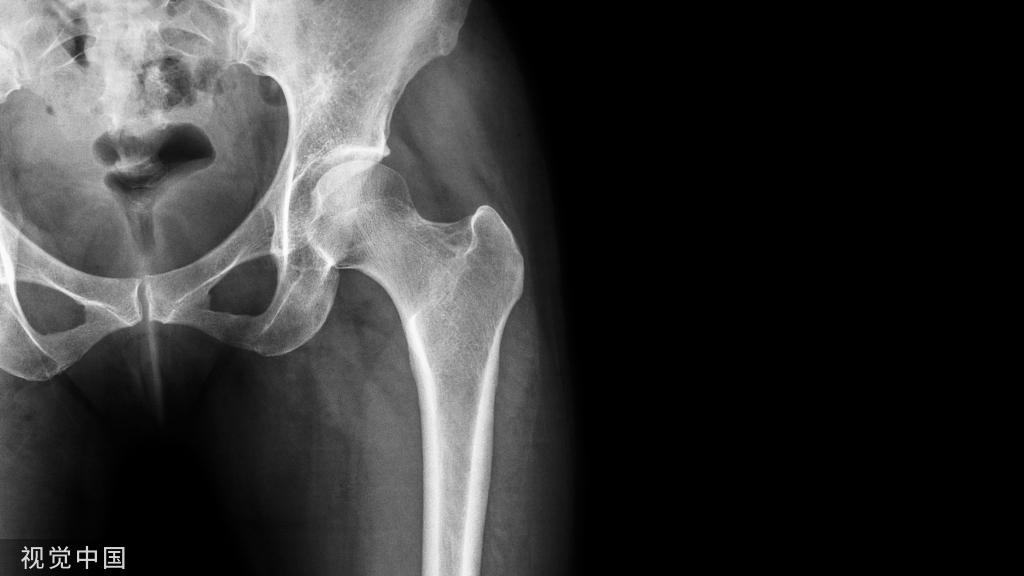

三、影像学检查1、X线检查X线检查用来评估肩峰形态,肱骨头和肩盂的关系,以及除外其他疾病。

图15 a.正常肩关节 b.肩峰撞击

图16 巨大肩袖损伤,肩峰下间隙<9mm